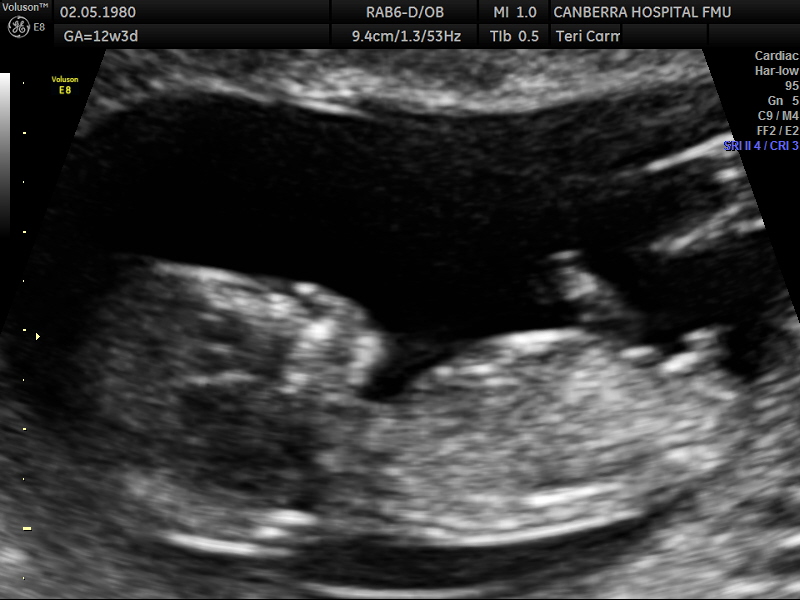

Its been ages once I've been on here but I'm back and pregnant!! I posted my pics on a FB nub theory page but didn't like their guesses :p (Lol!) so would love your thoughts. The scan was done at 12 weeks and 3 days but bub was measuring 13weeks exactly. Attachment 35124Attachment 35125Attachment 35126

Boy; stacking on last image and looks pretty short in second image x